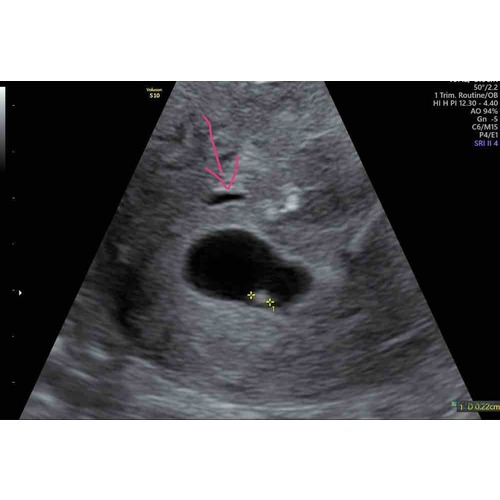

Nee boven de vruchtzak… 😃.. Ik heb er even een pijltje getekend..

Dat lijkt op een hematoom. Dat is een bloeding in de baarmoeder. Ik had het ook, maar bij mij zat het echt bijna tegen de vruchtzak aan. Bij jou zit ie een stuk verder weg. Kan zich vanzelf oplossen maar het kan ook dat je wat bloed verliest.

Lijkt een hematoom. Ik heb deze ook gehad bij mijn vorige zwangerschap. Ik verloor hierdoor na 7 weken veel bloed. Helaas met 10 weken misgegaan. Het gaat echter eerder goed dan slecht. Als je het niet vertrouwd even de verloskundige bellen. Kleine moeite, grote gerustheid.